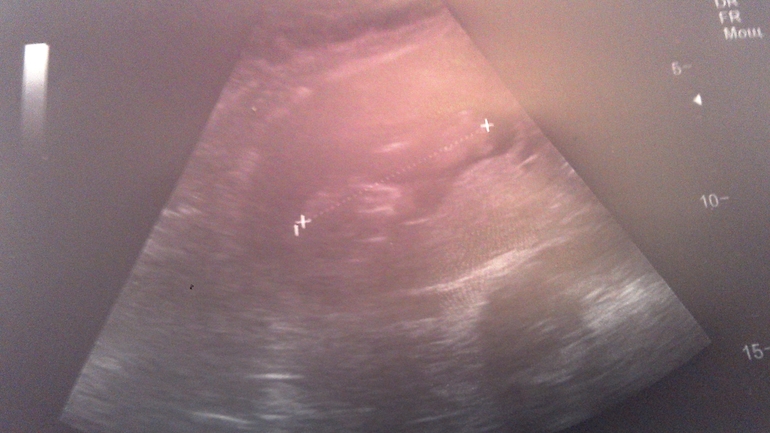

УЗИ 13-я неделя

Всё о нашей беременностиВчера разболелся живот, был тонус. появились светло желтые выделения. Позвонила врачу, она сказала такое бывает, если нет зуда не волноваться. Пить ношпу и вставлять папаверин. Сегодня проснулась и чувствую себя хорошо. Не выдержала пошла на УЗИ в Инвитро. Все хорошо, мы растем! Уже по 7 см, вертимся. Лежим в разных плодных яичках, но головка к головке. Наверное общаются))))) попробовали рассмотреть пол, хоть я и так знаю кто. Тот что по передней стенке вроде мальчик, но не точно.

Сегодня фото не очень, но запощу